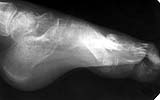

A colleague of mine from another facility presented a case of foot malunion (images attached) among other severe injury sequelae (there is also osteomyelitis of the femur and pelvic nonunion). The injury was 6 months ago. The colleague has some considerations about the other regions.

What about the foot - it is in stiff equinus and there is a pressure sore above the base of the Ist metatarsal bone. What treatment plan for the foot deformation you would choose? Just correct the equinus with external lfixator? Perform osteotomy of metatarsal bones? All or 1st only?